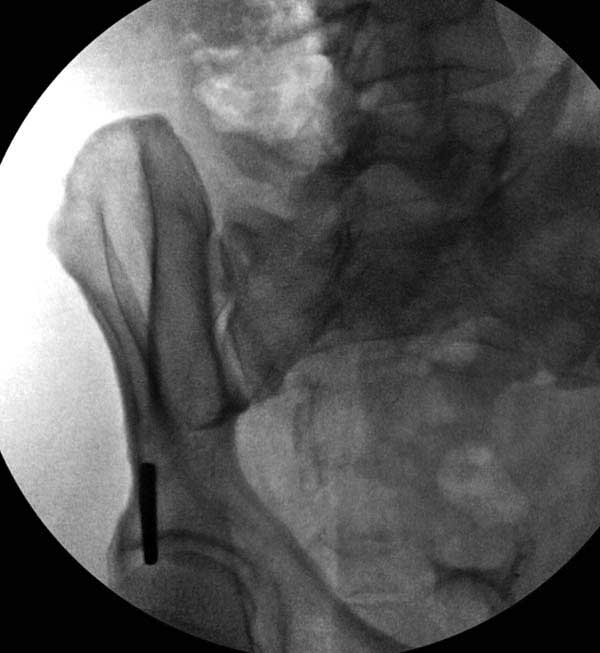

Здесь представлен случай 38 летнего больного (падение с высоты 9 метров) с нарушением тазового кольца. При поступлении для стабилизации передне-нижний аппарат наружной фиксации и на 6й день, вчера, операция из двух доступов.

Представлены снимки техники проведения стержней. Через место прикрепления прямой мышцы в Inferior Iliac Spine в направления вырезки создается жесткость. Weber clamp изнутри таза для репозиции, и фиксация после репозиции перелома крыла подвздошной кости. Наружный аппарат удален, нагрузка предполагается через два месяца.